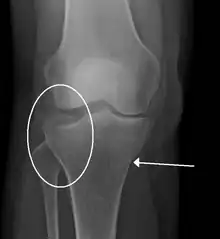

A tibial plateau fracture